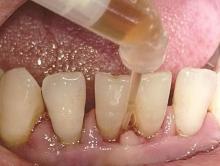

邵金龙, 吕春旭, 于洋, 等. 一步一步做好舒适化牙周基础治疗[J]. 中华口腔医学杂志, 2024, 59(5): 523-527.

Shao JL, Lü CX, Yu Y, et al. Comfortable initial perio-dontal therapy: step by step[J]. Chin J Stomatol, 2024, 59(5): 523-527.